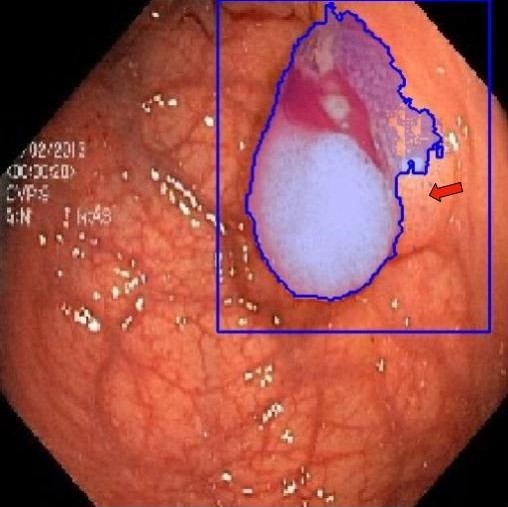

| Fine-Tuning | KvaSir [68] | 2D Endoscope | 1000 |

In 3D settings, we segment 2D slices and merge results for a 3D volume. We also benchmarked with 3D self-supervised methods from [86]. Tables (2) and (3) show that our two versions with ResNet-50 and Sam’s ViT hold the best records in each category. For instance, we outperform 2D SSL methods trained on the same dataset, surpassing foundation models such as SAM, Flava, and Clip. In the prompt-based settings, LVM-Med also delivers better performance compared with SAM. Second, LVM-Med achieves the best overall results on seven of eight segmentation tasks, mostly held by LVM-Med with ResNet-50. The improvement gaps vary on each dataset, for e.g., from on Kvasir and BUID compared with 2D supervised methods.